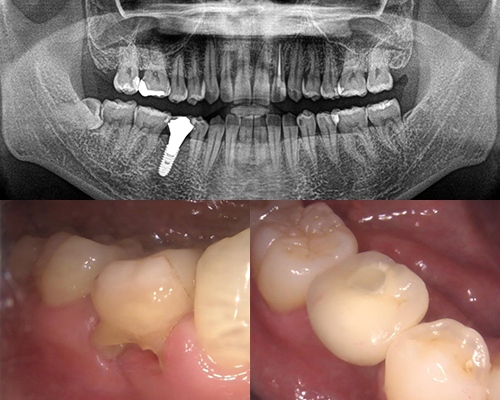

| 施術内容 | 右下の残存乳歯が保存困難なため抜歯。前後の歯が健全なため削らずに済むインプラント治療へ。 |

|---|---|

| 治療期間 | 8ヶ月(抜歯後治癒期間含) |

| 治療費 | 約40万円(ハイブリッドセラミック冠) |

| 副作用・リスク | インプラント治療は手術を伴います。腫れや痛みが少なくなるよう努力をしておりますが、多少の腫れや痛みが出ます。しかし、痛み止めで抑えられる程度ですのでご安心ください。 |

※表示は全て税込表示です。